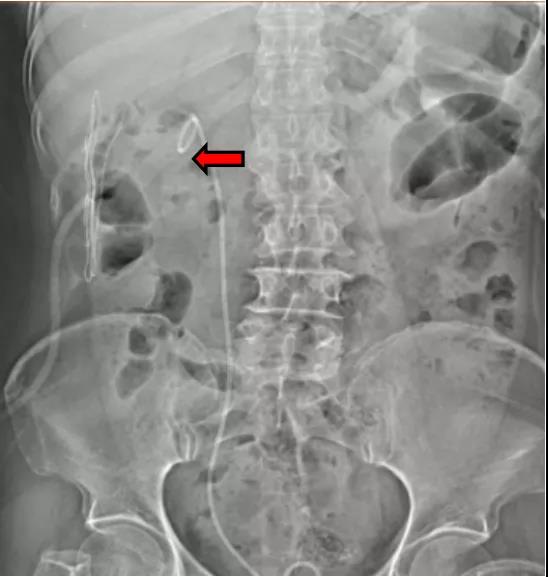

重庆的陈女士今年60多岁,8年前因腰痛在当地医院就诊,超声检查发现右肾铸型结石。前段时间陈女士腰痛加重,为此跑遍大江南北,咨询多家医院均建议手术治疗,听闻北京大学第三医院延安分院有北京专家长期坐诊并驻扎医院参与查房和手术,经过多方面考量后,于是专程选择来延安住院接受治疗。

北京驻延泌尿外科专家郝一昌教授介绍说:陈女士罹患的肾结石,体积大、负荷高,在肾内分布广泛,占据了多个肾盏,这类结石被学术界称为复杂性肾结石,也叫铸型结石或鹿角形结石。这种类型的结石“复杂”在哪儿呢?做个比喻来说,如果把肾脏比喻成一所大房子的话,这种类型的肾结石,把房子中间的大厅(肾盂)和周围的各个房间(肾盏)都占据了,极大影响了肾脏的功能,如果不及时治疗,会对肾脏功能造成严重的损害。通过同步多镜联合泌尿系结石碎石取石术技术,术中对患者陈女士只建立了一个经皮肾镜通道,双镜联合清除了肾内所有的结石,是一项很好的技术突破。